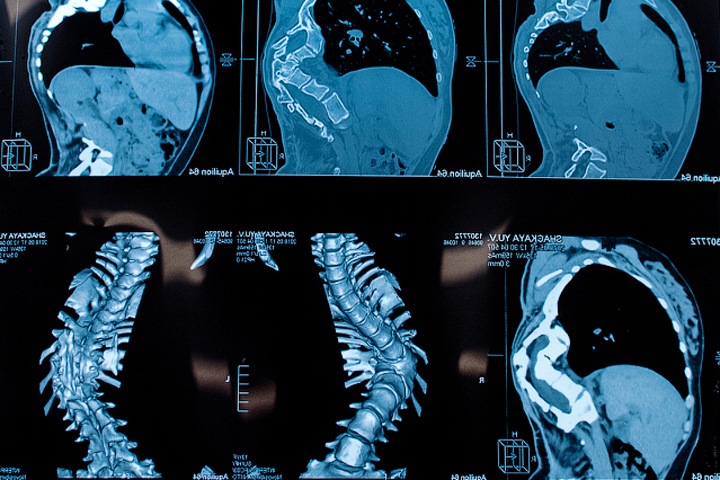

По данным журнала «Сибмеда», сколиоз — заболевание, при котором искривляетсяпозвоночник. Оно имеет четыре степени, которые определяют по данным рентгена в зависимости от градуса кривизны. Сколиоз бывает врожденный и приобретенный. Развивается у детей школьного возраста. У 80% школьников точная причина сколиоза отсутствует. В России детей, которым ставят такой диагноз, — 0,4%.